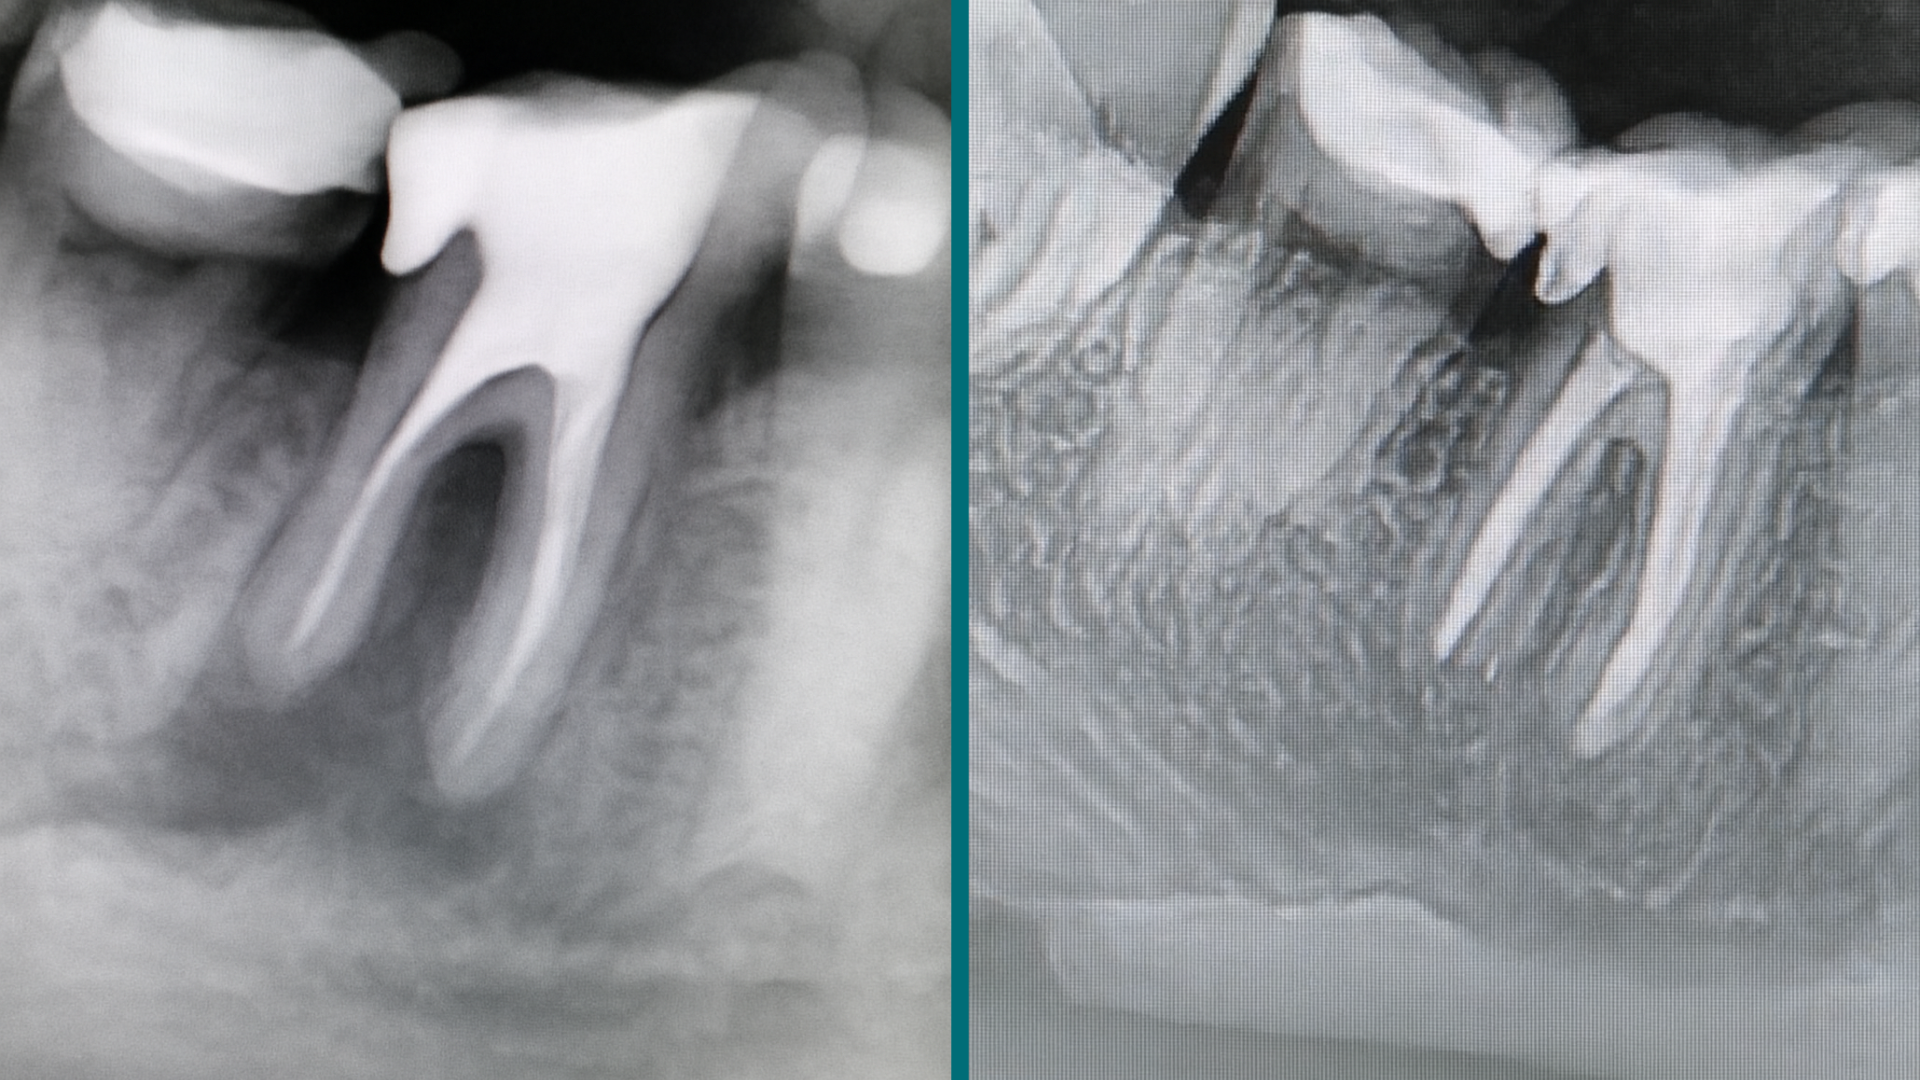

- Responde a las preguntas sobre la imagen.